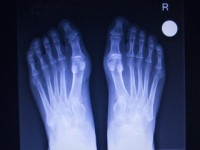

外反母趾の治療と改善方法

足のつけ根に痛みがともなう外反母趾は、早めの対策が改善につながります。ここでは、外反母趾の病院での治療法や、自宅でできるセルフケア、マッサージなどについて、ドクター監修のもと解説します。